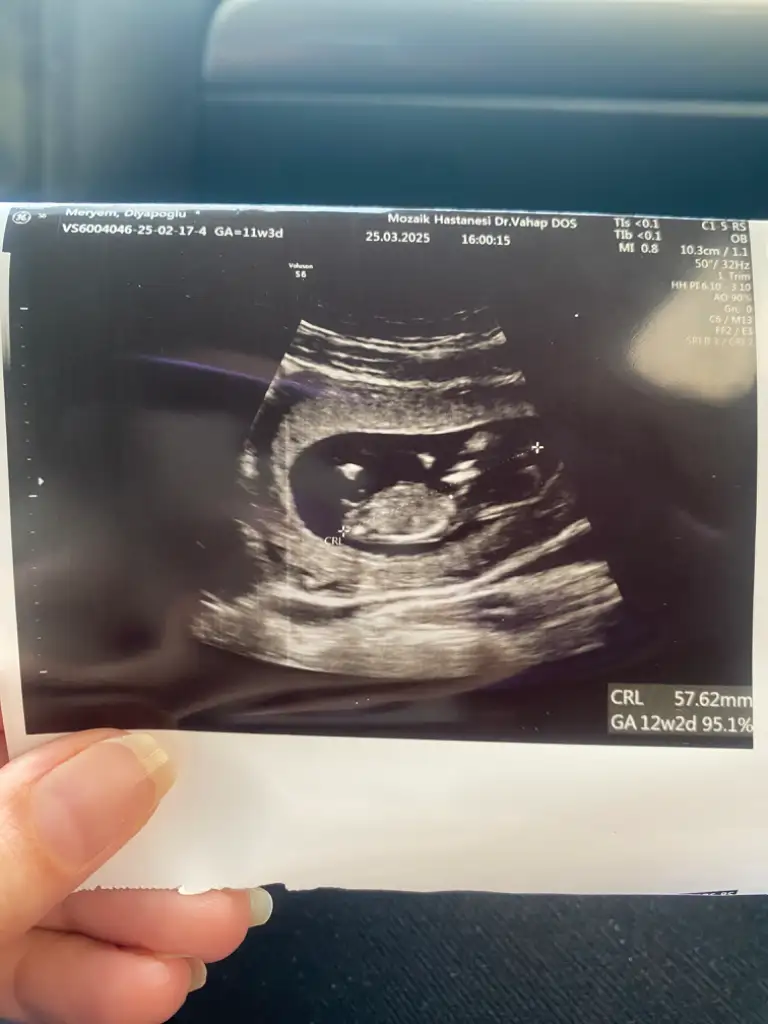

Bana da bakar mısınız. Doktor tahminde bulunayım dedi ama parti istediğimiz için söyletmedik. 11. Hafta

• IMG_8585.webp

29,5 KB · Görüntüleme: 511